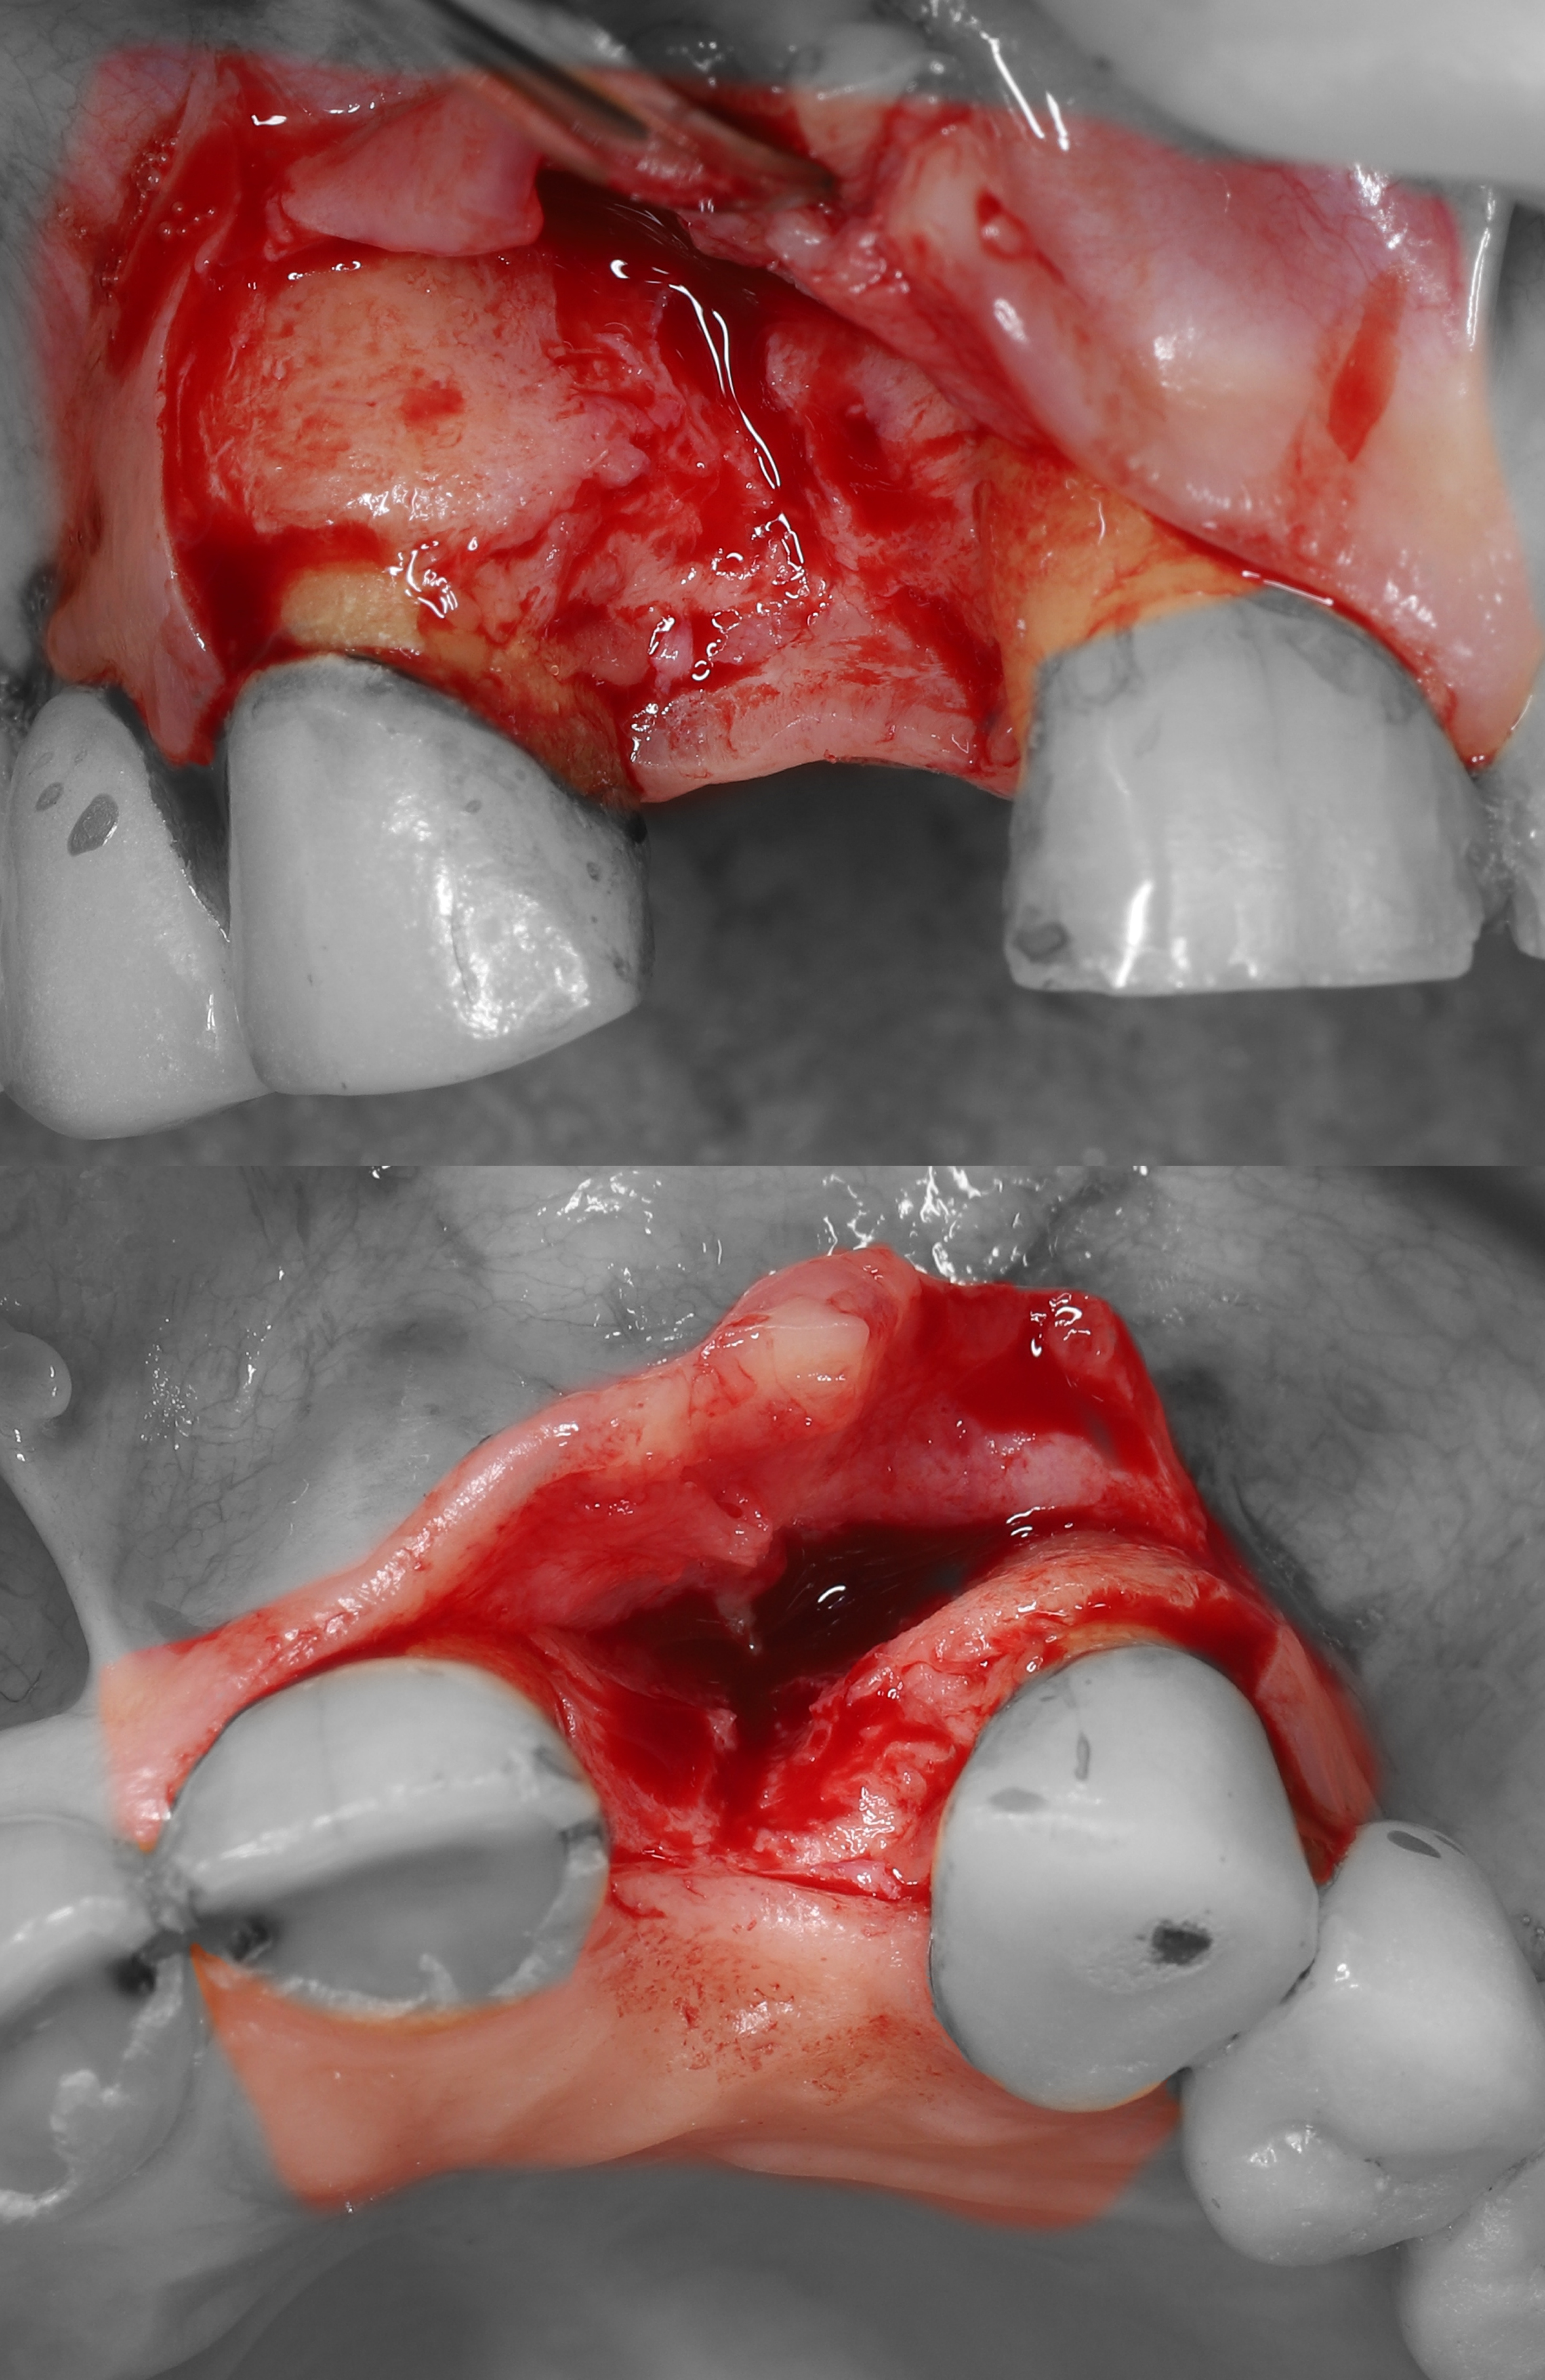

1) Дано: вторичное отсутствие зуба 1.2, выраженный дефект вестибулярных мягких и твердых тканей.

2) Проведены крестальный и вертикальный дистальный разрезы, отслоен СНЛ.

5) Из области бугра ВЧ был получен кортикально-губчатый трансплантат.